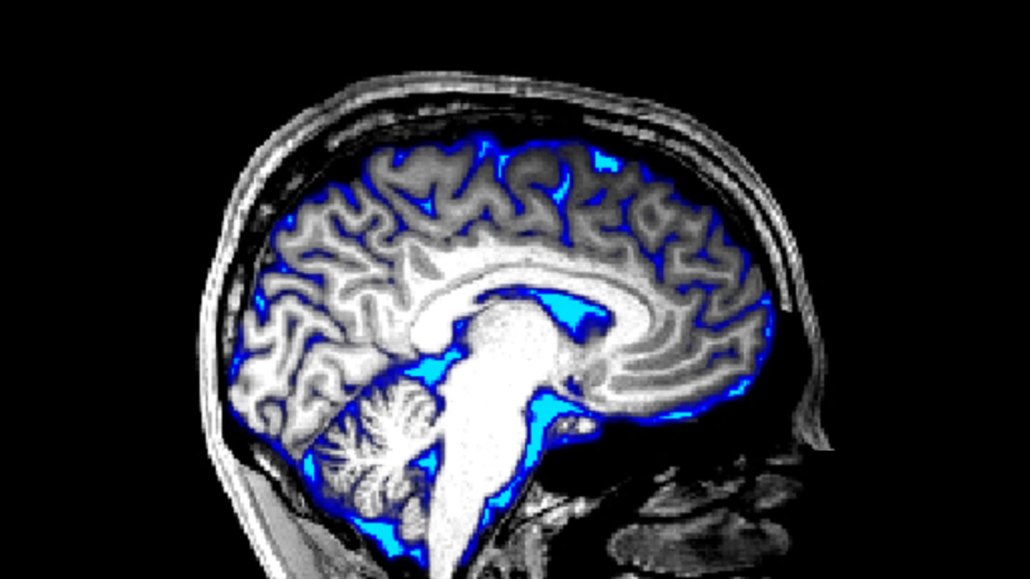

A MRI image of a brain shows regions of cerebrospinal fluid in blue.

S.D. Williams (CC-BY 4.0)